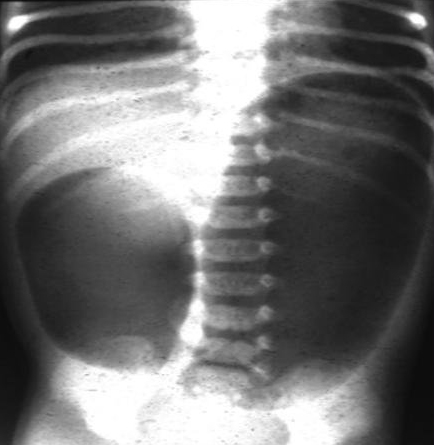

Abdominal x-ray demonstrating double bubble gas pattern consistent with duodenal atresia

From the collection of Dr KuoJen Tsao; used with permission